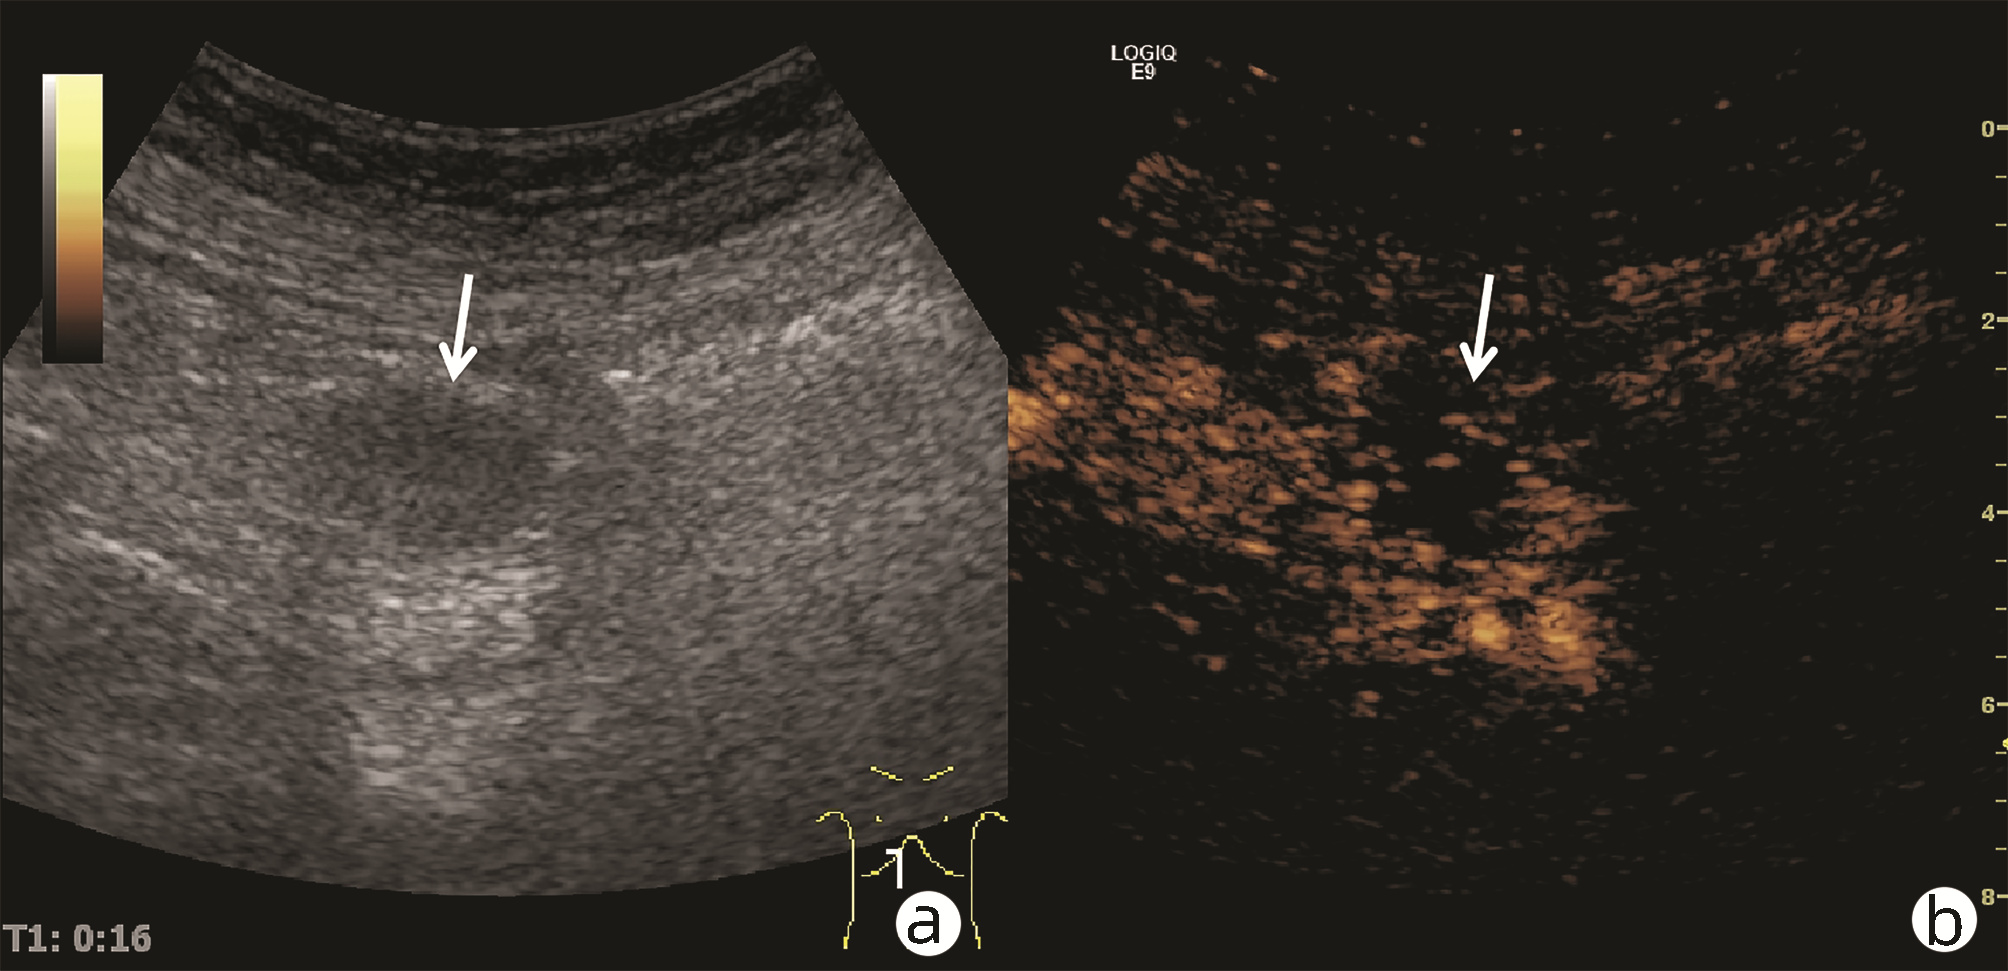

Ultrasound findings and contrast-enhanced ultrasound findings of mass-type autoimmune pancreatitis versus pancreatic ductal adenocarcinoma

Xiangliu OUYANG, Yunxia HAN, Lichun ZHENG, Yingchun ZHAO, Xinyu SHEN, Wenjun ZHANG, Yanbin WANG

2022, 38(6): 1351-1355. DOI: 10.3969/j.issn.1001-5256.2022.06.025

Abstract(1465) HTML (554) PDF (3738KB)(58)

Abstract:

Objective  To investigate the value of ultrasound and contrast-enhanced ultrasound (CEUS) in the differential diagnosis of mass-type autoimmune pancreatitis (AIP) and pancreatic ductal adenocarcinoma (PDAC).  Methods  A retrospective analysis was performed for the clinical data, ultrasound findings, and CEUS findings of 11 patients with mass-type AIP who were diagnosed in Tangshan Workers' Hospital from January 2015 to December 2020, and their characteristic manifestations were analyzed and compared with the data of 23 patients with PDCA. The chi-square test was used for comparison of categorical data between two groups.  Results  For the 11 patients with mass-type AIP, CEUS had a diagnostic accuracy of 63.64%, and all of these patients had hypoechoic single lesions; the patients with clear boundaries, regular morphology, pancreatic duct dilatation or cutoff, and blood flow signal accounted for 54.55%, 63.64%, 18.18%, and 36.36%, respectively, while in the PDCA group, such patients accounted for 30.43%, 34.78%, 78.26%, and 21.74%, respectively, and there was a significant difference in the presence or absence of pancreatic duct dilatation or cutoff between the two groups(χ2=11.089, P < 0.05), with no significant differences in the other indices (all P > 0.05). For the 11 patients with mass-type AIP, CEUS showed that 7 patients (63.64%) had hyperenhancement and 4 (36.36%) had iso-enhancement in the arterial phase, and 5 patients (45.45%) had hyperenhancement in the arterial phase and 6 (54.55%) had iso-enhancement in the venous phase; for the 23 patients with PDCA, 22 (95.65%) had hypoenhancement of lesions in both arterial and venous phases, and there were significant differences in the enhancement pattern in arterial and venous phases between the two groups (χ2=30.345 and 30.084, both P < 0.05).  Conclusion  The enhancement pattern of CEUS and the presence or absence of pancreatic duct dilatation or cutoff have a relatively high value in the differential diagnosis of mass-type AIP and PDCA.